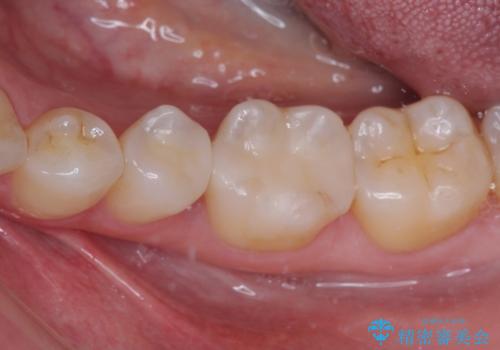

自然な色調で大変満足されました。